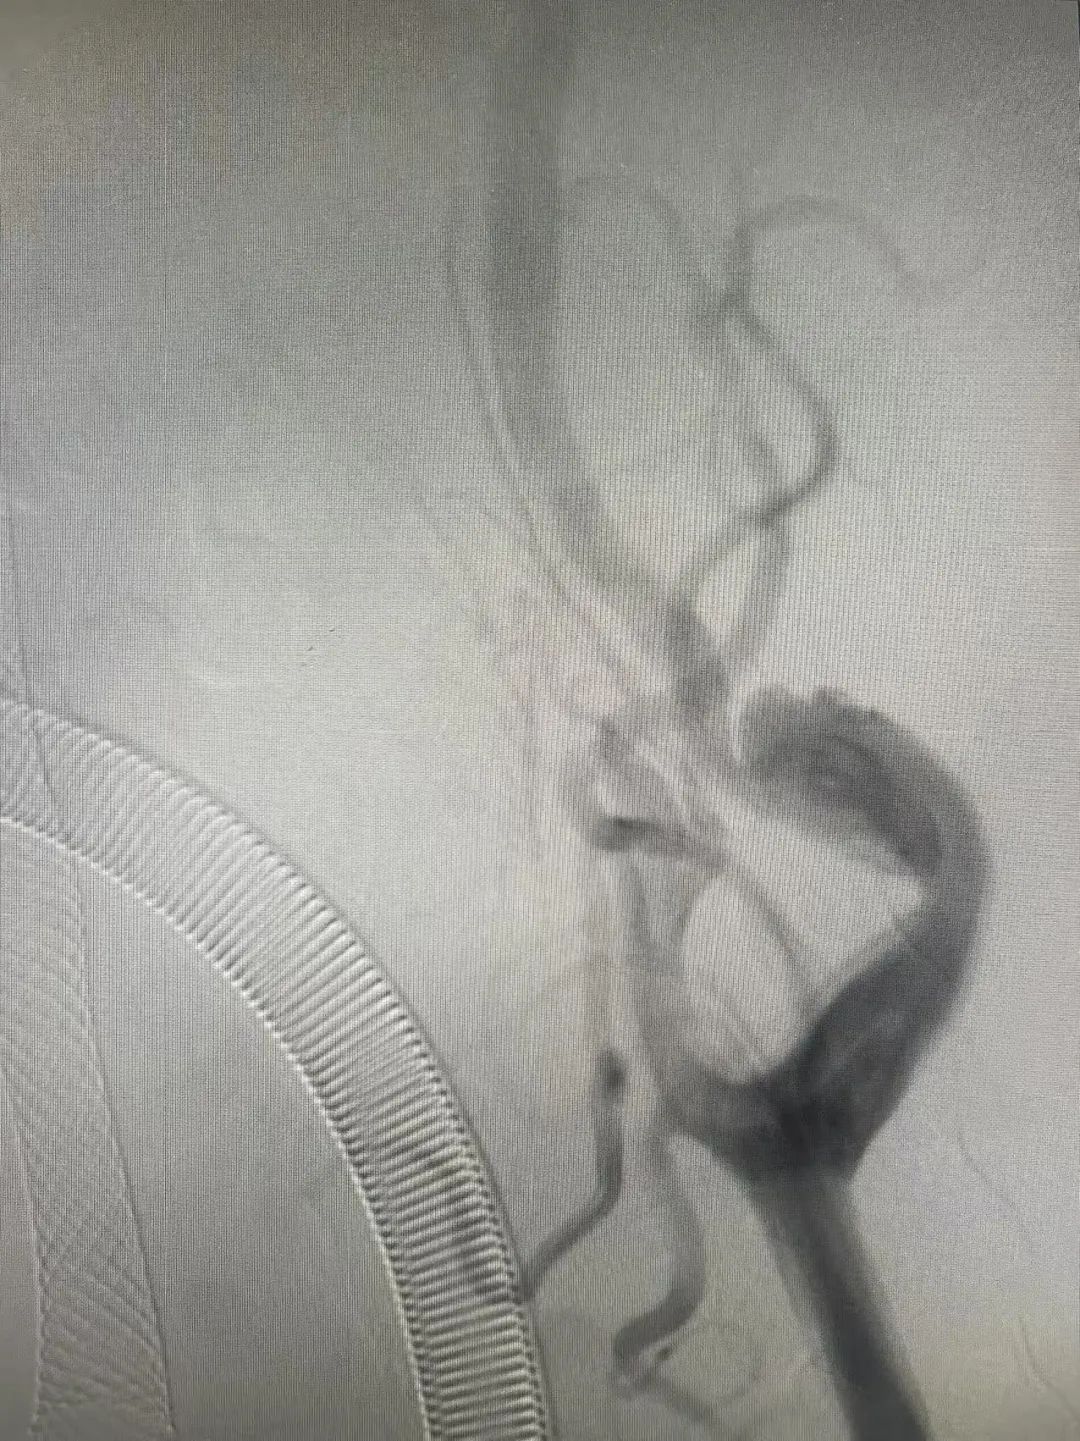

Y先生术前血管

Y先生术后血管